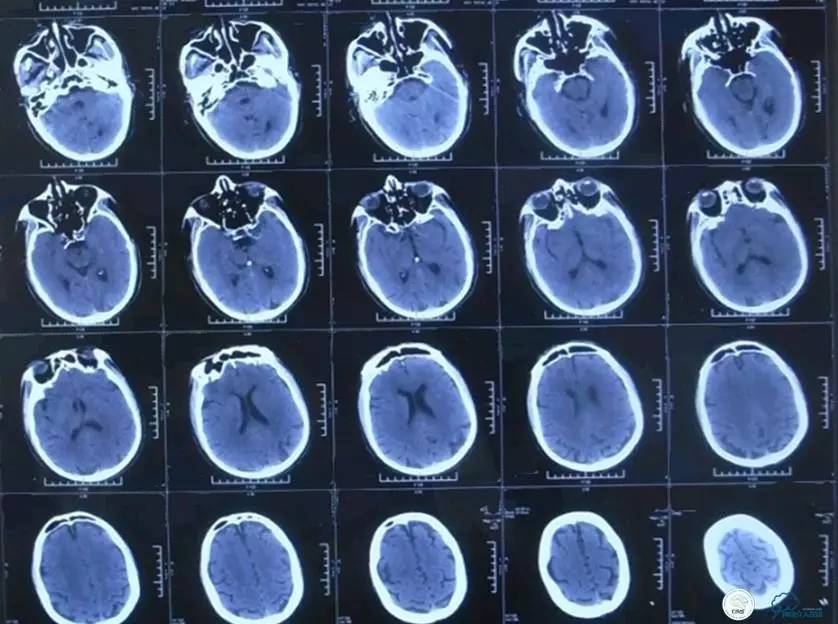

▼2015-06-05颅脑CT

患者时间窗内,发病3h开始静脉溶栓。rt-PA9mg/kg,70mg,7mgIV;63mg微量泵注入1h。期间患者症状改善不明显。观察时间后,仍无改善。遂介入交接治疗。

2015-06-05脑血管造影:左侧颈内动脉闭塞。

评估患者侧支循环,考虑患者发病时间超过6个多小时,未行血管内治疗。

▼2015-06-05颅脑MRI

▼颅脑CT

▼2015-06-13颅脑CT

患者症状稳定,遗留有失语及右侧肢体活动不灵。